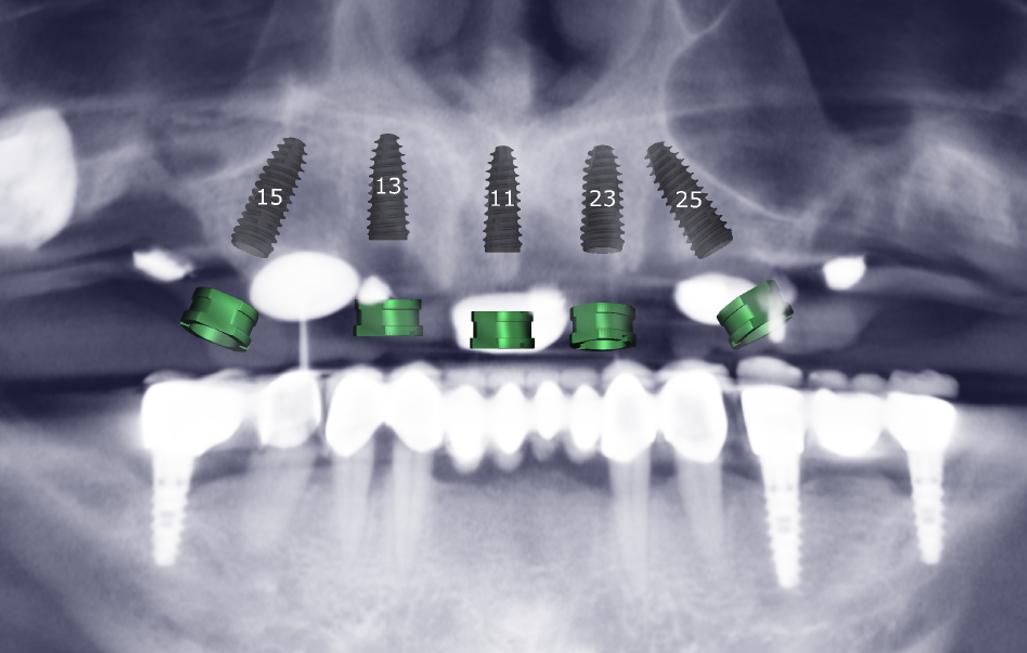

3D Planlama Önizlemesi

Alınan kayıtlarla oluşturulan sanal hastada ameliyat öncesi analiz imkanı

Sanaldan cerrahiye sapma minimizasyonu

Sinir, sinüs, kök mesafelerinin 3B değerlendirilmesi ve komplikasyon riskinin azaltılması